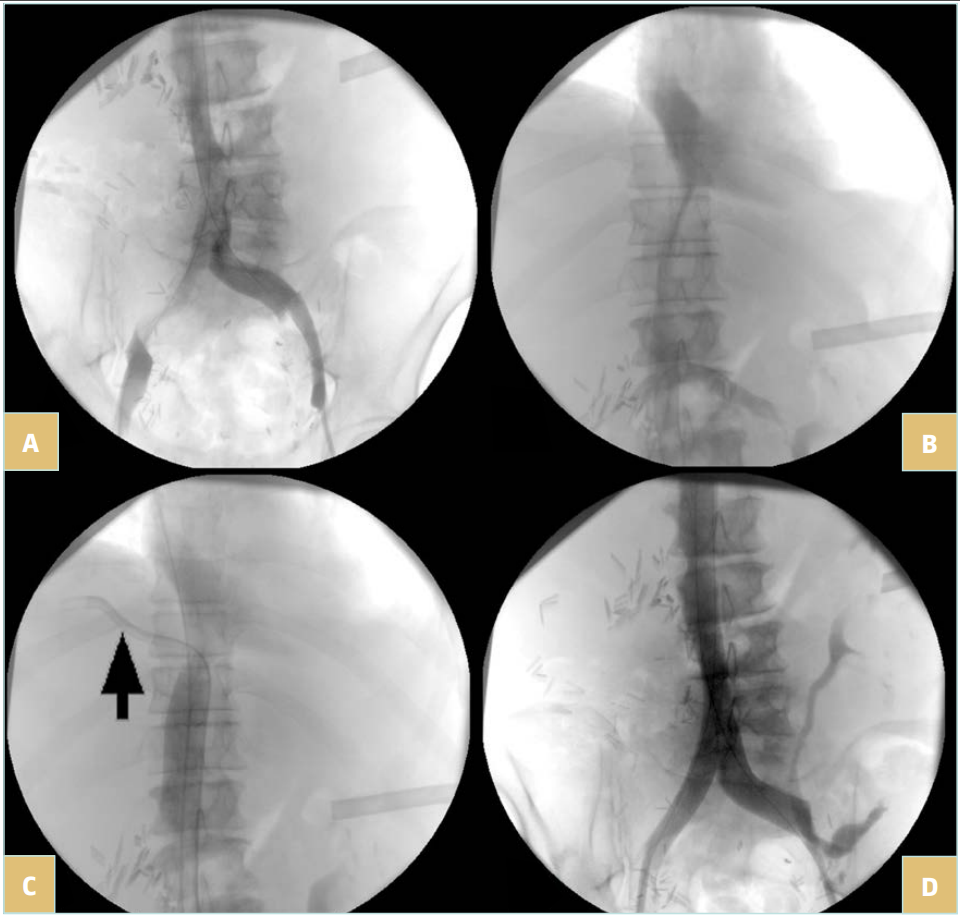

Once the lesion is crossed (Figure 4A and 4B), super stiff or extra stiff guidewire and then a larger sheath are inserted (10-12 Fr depending on balloon and stent needs) and intravenous heparin should be given at the dose of 50 UI/kg. At this time, IVUS can be used to ensure a better evaluation of the lesion.6 Pressure gradient measurements can be performed but have value only if positive (the absence of pressure gradient can be due to collateral pathways, even more in a patient that is lying down). Then predilatation is performed using high-pressure balloons of progressive diameter mainly in case of postradiotherapy lesions (in these cases, downsizing by 2 mm in diameter compared with a standard procedure is recommended to avoid venous rupture).

Stenting is then performed using self-expanding stents (Figure 4C and 4D). Different stents were used in the literature. Until 2010, Wallstent (Boston Scientific, Marlborough, Massachussetts, USA) and Gianturco Z stent (Cook Medical, Bloomington, Indiana, USA) were the 2 most used stents. Since the development of nitinol self-expanding stents, many others have become available, though some of them are designed for femoro-iliac veins (Venovo, Abre). Stent sizing depends not only on the diameter of the adjacent nonpathologic IVC size—that can be evaluated by CT scan or IVUS—but also to the tumor. In most cases 18 to 22 mm in diameter should be used for the IVC as larger stents can have difficulties with expanding; too-small stents can migrate and also limit flow. Few nitinol stents are available in 20-mm diameter or higher (see Table I). These stents have a more precise deployment than the Wallstent without foreshortening. Regarding stent length, they should cover at least 15 to 20 mm beyond the obstructive lesion at both ends, covering an area that goes not only from healthy-to-healthy segment but also includes a safety margin to avoid restenosis by tumor progression.9,10 When multiple stents are needed, an overlap of at least 20 mm should be used. In case of biiliocaval lesions, different stent configurations can be used: the Eiffel tower configuration while deploying the IVC stent first, then both iliac stents simultaneously (Figure 4D), or a double-barrel technique (mostly if lesions are limited to the iliocaval confluence).

Figure 4. 76-year-old man suffering from right iliac and inferior vena cava (IVC) compression by iliac and infrarenal IVC nodes and liver metastasis from urothelial cancer with ascites (history of cystectomy and right uretero-nephrectomy): A) compression of the right iliac vein and infrarenal IVC; B) compression of the suprarenal IVC; C) after angioplasty and stenting of the suprarenal IVC; a guidewire (arrow) was positioned in the suprahepatic vein before stent deployment; D) after

biiliocaval stenting according to the Eiffel tower technique.

In these patients, prognosis mainly relies on the oncologic status and can be excellent when the cancer is cured (Figure 5). Therefore, results of stenting in terms of clinical outcome and patency rates should be comparable to nonmalignant lesions.

Figure 5. 44-year-old man suffering from symptomatic inferior vena cava (IVC) (lower-limb edema) occlusion due to retroperitoneal fibrosis occurring after liver tumor resection: A) IVC occlusion; B) result after recanalization and stenting with 2 Wallstents of 16 mm in diameter. Patient remained asymptomatic at 108 months of follow-up.